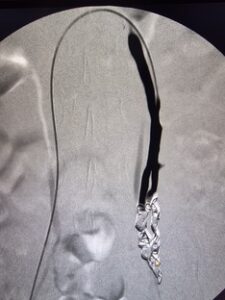

Η θεραπεία εκλογής για το σύνδρομο πυελικής συμφόρησης είναι η ενδαγγειακή αποκατάσταση με τη χρήση ελασμάτων (coils). Ουσιαστικά, πρόκειται για μια ελάχιστα επεμβατική μέθοδο, που αποσκοπεί στην κατάργηση των προβληματικών φλεβών με αρκετά ικανοποιητικά αποτελέσματα. Πρόσφατα, δημοσιεύτηκε στις κατευθυντήριες οδηγίες της Αγγειοχειρουργικής κοινότητας και στο Αμερικάνικο φλεβολογικό Forum, ως προτεινόμενη θεραπεία για την αντιμετώπιση της νόσου , η ενδαγγειακή αποκατάσταση με εμβολισμό.

case 2

φλέβας με ύφεση συμπτωματολογίας